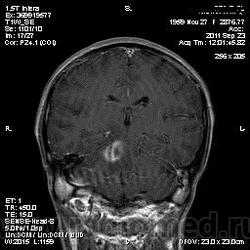

Похоже на метастазы

Тоже за метастазы. Достаточно большой отек при небольших образований.

я тоже думаю про метастазы, но уж сильно много сомнений.... и как будто бы капсула в субтенториальном очаге на нативных снимках, и на кт вроде бы как на абсцесс похоже.....

В данном случае был дифф. диагноз с абсцессом головного мозга (вариант сепсиса тоже рассматривался), т.к у пациента была и лихорадка и ЛОР-патология; но учитывая количество очагов (если смотреть все МР-снимки, выявляется ещё 2 мелких очага в коре) не исключено наличие метастазов + периферических характер накопления- можно предполагать и то и другое.

Это абсцессы. Равномерной толщины стенки, ровные контуры. На Т2 содержимое полостей имеет средний уровень сигнала - для абсцессов это характерно. Для дифференциации нужно было сделать DWI, тогда гной имел бы повышенный уровень сигнала. Хороший аппарат, почему не сделали?

Метастазы при отсутствующем онкоанамнезе в среднем возрасте бывают все же редко. К тому же лихорадка, лейкопения как проявление снижения иммунитета.

выложила ДВИ, жаль не построить ИКД. Очаг на 16 срезе Т2 виден на постконтрастном срезе 3 в сагиттальной проекции; в коре теменной доли есть ещё два мелких очага, непопавших на данные снимки.

Первичной опухоли не выявлено: нейрохирурги за абсцесс, неврологи- энцефаломиелит. Мужчина тяжёлый, берут ликвор на все возможные вирусы и бактерии.

пришла положительная ф50 и ликвор с токсоплазмой

"мнрогоочаговое поражение головного мозга супра/субтенториальной локализации. Дифференциальный диагноз с инфекционным, метастатическим поражением головного мозга"